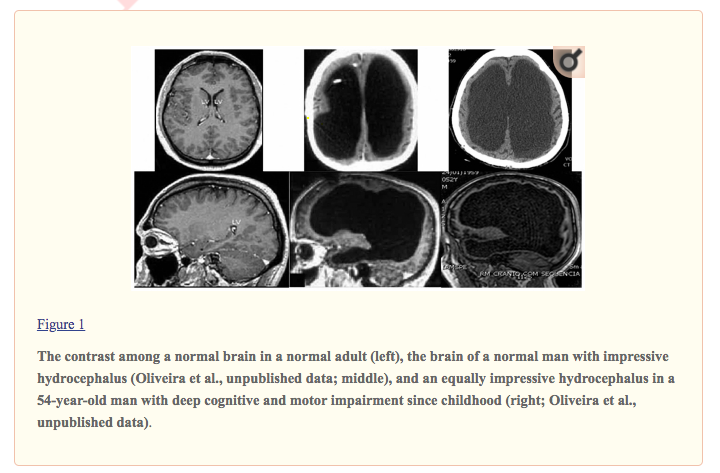

Many cases of humans that are by all appearances normal but missing massive volume of brain parenchyma like the middle figure here.pic.twitter.com/u8zt9G2tDg

You find the critical/essential areas deeper in the brain. They also are the most "ancient" (evolutionarily) and most conserved (you find similar areas in many other species). Speaking very generally, the thinking is- If the change happens over time our brain adapts. ...

... So, if brain tissue is pushed or compressed slowly over time (hydrocephalus or a tumor, for example) then our brain is plastic enough to compensate, at least to a degree. And there are some extreme examples of this.

what’s weird to me is that we need the brainstem, we need the limbic system, but (almost?) all the tissue here is on the outer layers... amazing if it really can just progress slowly like this and you can end up with a functional human with just a big gap... really astonishing

We have a very crude notion of what is normal and normal functioning. The functioning part is in the outermost layer called cortex. But even now we have seen cells can communicate without being chemically/physically connected, with electromagnetic waves. =D brain is amazing!